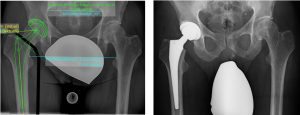

(Bilder oben v. links: Knorpeldefekt, Knorpelzelltransplantation)